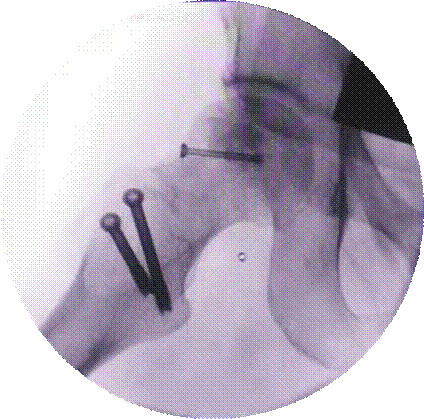

关节镜下肩袖损伤修复术治疗肩袖损伤

优点:损伤小、恢复快。